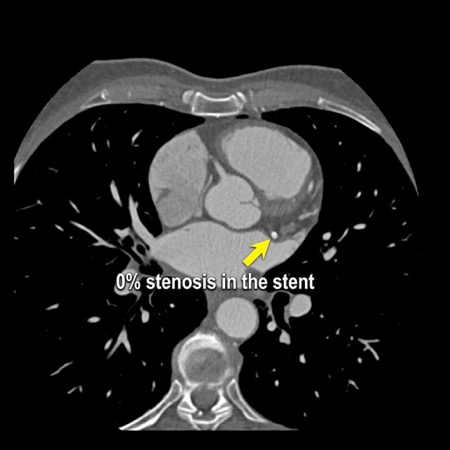

Modifier S – stent

The presence of a stent is indicated by modifier “S”.

Examples

- If a patient has a stent, showing no in-stent restenosis and a mild

(25-49%) stenosis in the coronaries, this patient classifies as CAD-RADS

2/S. - Similarly, a patient with no in-stent restenosis but severe (70-99%)

stenosis in a coronary other than LM classifies as CAD-RADS 4A/S. - If there is a severe (70-99%) in-stent restenosis in a coronary other

than LM, this patient classifies as CAD-RADS 4A/S. - If the stent is non-diagnostic and there is no >49% stenosis present

in the coronaries, the patient classifies as CAD-RADS N/S.

Note: the location of the stenosis does not matter, when using

CAD-RADS.

What matters is that the patient has a severe stenosis and needs further

management.

Please note: total coronary plaque burden should also be added and is

placed before the modifier S.